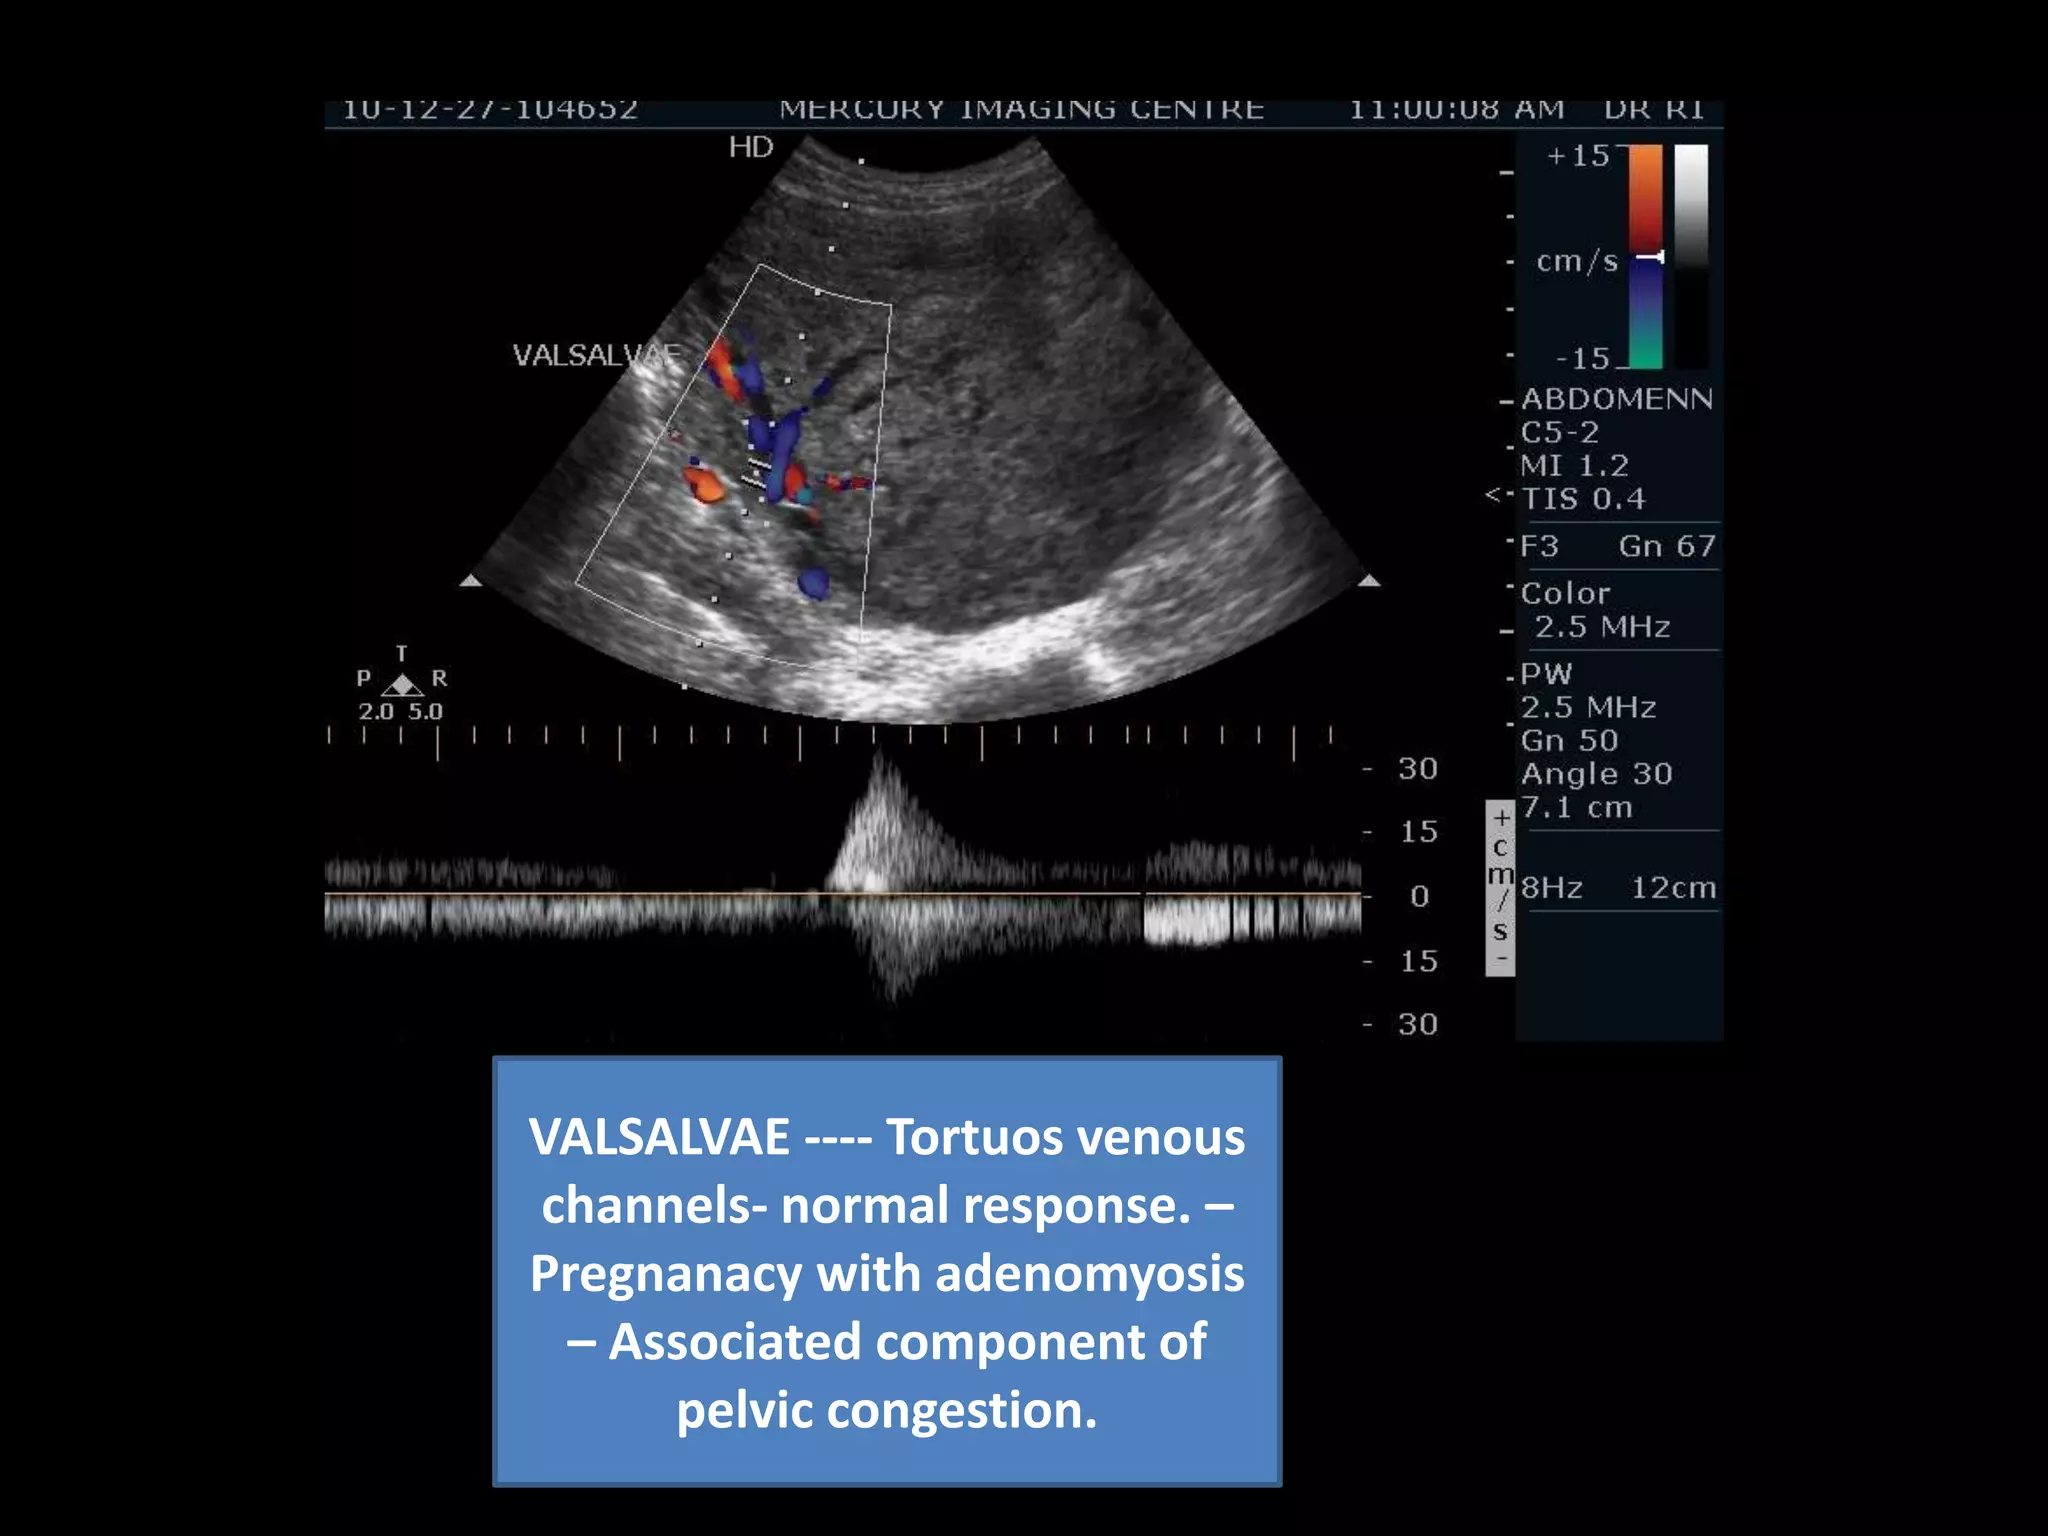

Congested  venous system.

Pregnancy with adenomyosis and leiomyoma with component of pelvic congestion

VALSALVAE ---- Tortuosvenous channels- normal response. – Pregnanacy with adenomyosis – Associated component of pelvic congestion.